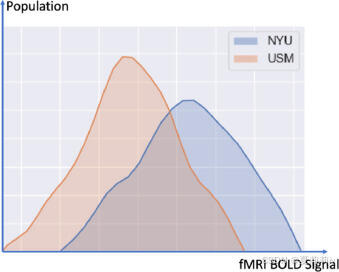

②Different data distribution on different sites:

①Sites chosen: the largest four, UM1、NYU、USM、UCLA1 with 106, 175, 72, 71. Eliminating incomplete data samples, left 88, 167, 52, 63 each